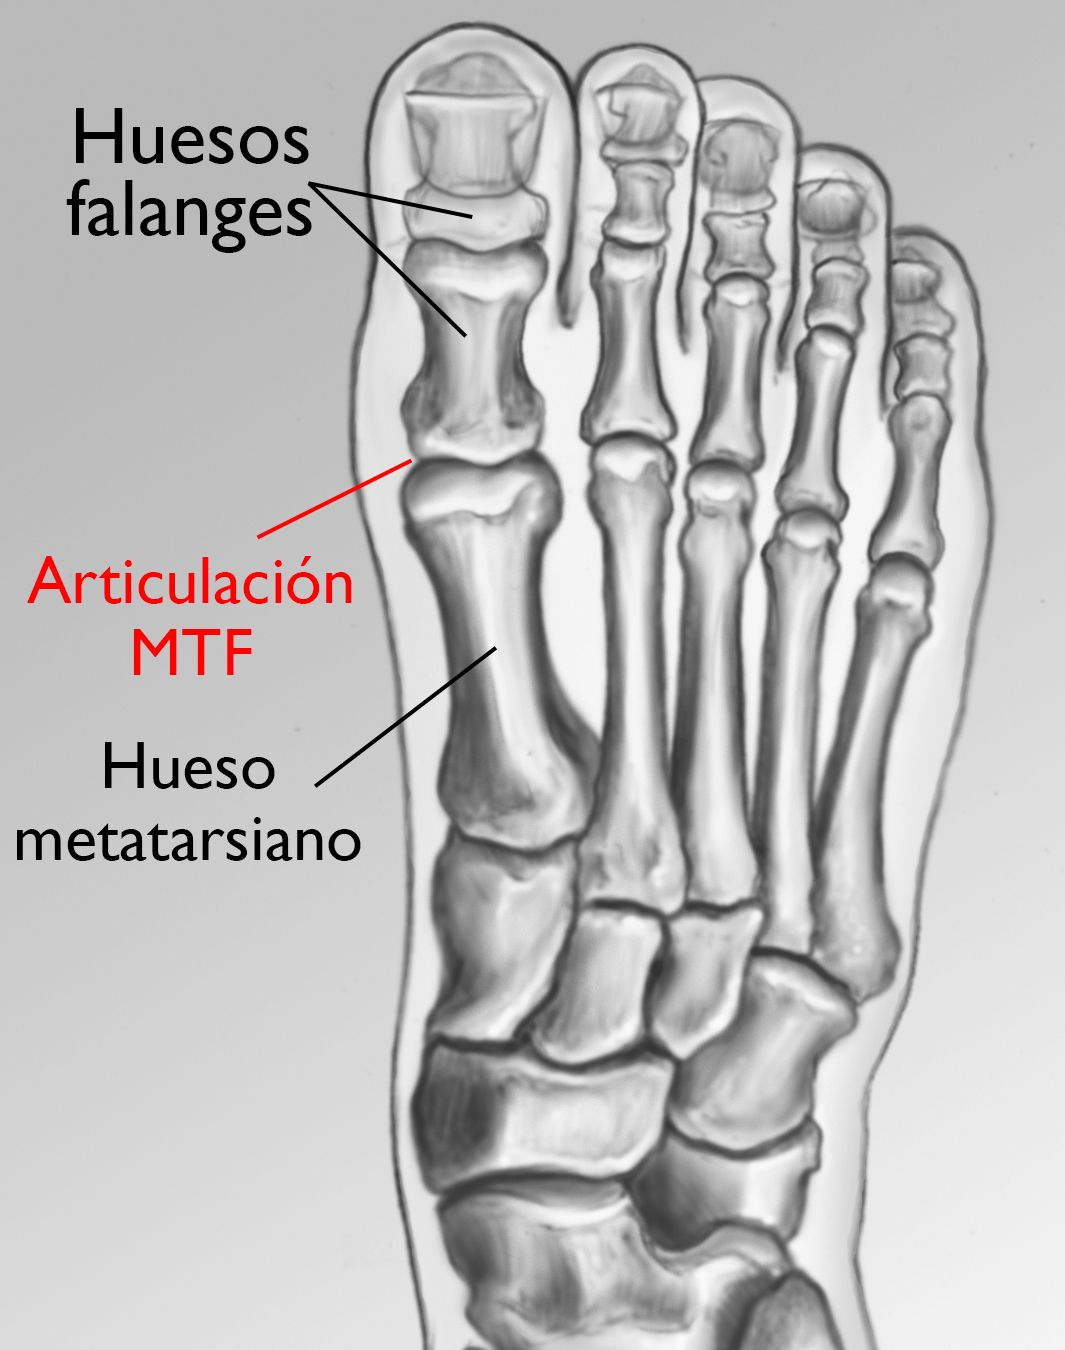

Anatomía

El dedo gordo está conformado por dos articulaciones. La más larga de las dos es la articulación metatarsofalángica (MTF), donde el primer hueso largo del pie (hueso metatarsiano) se une con el primer hueso del dedo (falange).

Los juanetes se desarrollan en la articulación MTF.

Los huesos del pie y la articulación metatarsofalángica (MTF).